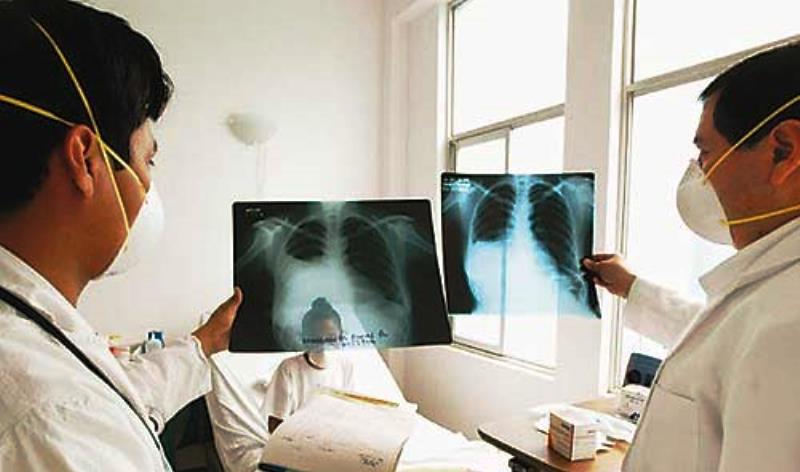

Chimbote en Línea (Salud).-Más de 4,000 casos nuevos de tuberculosis (TB) atiende cada año EsSalud en todo el país, situ...